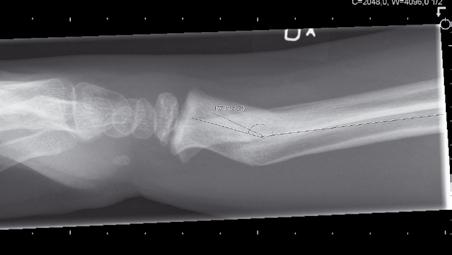

På onsdagsmorgonen gick Yngvar Krukhaug, Bergen, på ett didaktiskt sätt igenom eviden sen för olika behandlingsstrategier av distala radiusfrakturer. ”Take home message” blev att de data vi grundar våra beslut på generellt är av undermålig kvalité, att gipsbehandling kan användas i 80 % av fallen och att det nu finns evidens för användning av volar plattfixation vid instabila AO C1 och C2 frakturer. Vid mer splittrade frakturer finns inga data som visar att volar platta är bättre än externfixation, nå got som ytterligare diskuterades vid efterföl jande symposium om indikationer för vinkel stabila plattor med Ingvar Allvin, Örebro, som moderator.

Ortopedtraumatologiska sällskapet och Svens ka skulder- och armbågssällskapet med mo derator Per-Olof Josefsson, Malmö, fortsatte med en grundlig genomgång av behandlings strategier vid traumatiska armbågsskador. Lars Adolfsson, Lindköping, underströk i sitt anförande att distala humerusfrakturer hos vuxna ofta är svårbehandlade och bör skötas av få individer som kan skaffa sig erfarenhet av frakturtypen. Frakturer bör handläggas dag tid och inte i blodtomt fält då operationerna ofta tar lång tid. Rekommendationen blev att använda två parallella plattor, en på medialoch en på lateralsidan av distala humerus, då denna teknik bättre fångar och fixerar splittra de fragment än vinkelrätt anbringade plattor. ”Triceps split” rekommenderades som frilägg ningsteknik medan olecranonosteotomi oftast bör undvikas.